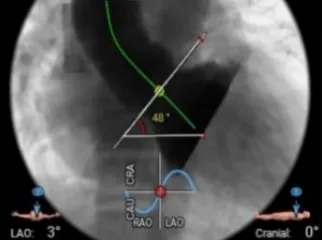

左右窦重合体位造影

瓣膜完全释放